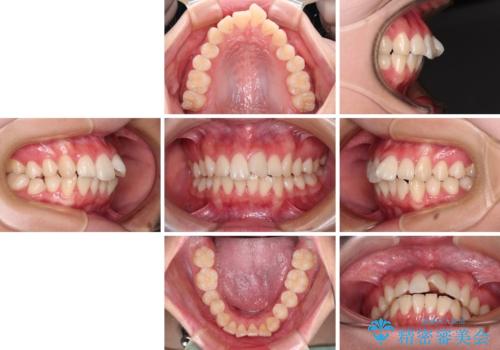

- 前歯がくちばしのように飛び出していることを気にして来院された患者様です。

唇が前方に突出している横顔が気になっているため、上下左右の第一小臼歯4本を抜歯し、ワイヤー装置にて矯正治療を行うこととしました。

わずか2年弱で一気に口元が変化し、患者様には大変満足していただけました。